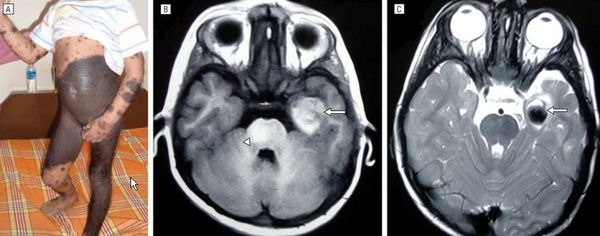

В легких везикулярное дыхание, хрипов нет. Тоны сердца ясные, ритмичные. Артериальное давление — 120/80 мм рт.ст., пульс — 76 ударов в минуту. Живот мягкий, безболезненный при пальпации. Печень у края реберной дуги. Симптом Пастернацкого отрицательный с обеих сторон. Физиологические отправления в норме. Периферические лимфатические узлы не пальпируются. Патологический процесс занимает обширные участки на коже туловища, конечностей, представлен высыпаниями темно-коричневого цвета с бугристой, бородавчатой поверхностью, участками выраженного гипертрихоза, местами определяются трещины кожи. При осмотре выявляются невусы средних размеров, диаметром 1,5 см, в виде разбросанных папул на коже живота (рис. 1—4). Рисунок 1. Высыпания гигантского невуса на коже живота. Рисунок 2. Высыпания гигантского невуса на коже туловища и правого бедра. Рисунок 3. Высыпания гигантского невуса на коже спины. Рисунок 4. Очаги меланоцитарного невуса на коже боковой поверхности туловища и передней поверхности правого бедра. Слившиеся крупные очаги занимают всю поясничную область, боковую правую поверхность туловища и переходят на область правого бедра, где гипертрихоз выражен в большой степени (рис. 5—6). Рисунок 5. Очаги меланоцитарного невуса на коже поясничной области и задней поверхности правого бедра. Рисунок 6. Высыпания гигантского волосяного невуса на коже спины и правого бедра.